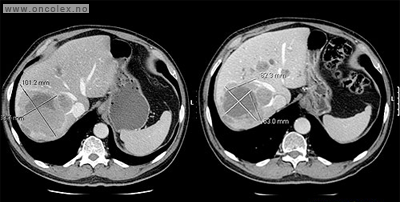

Bildeeksempler